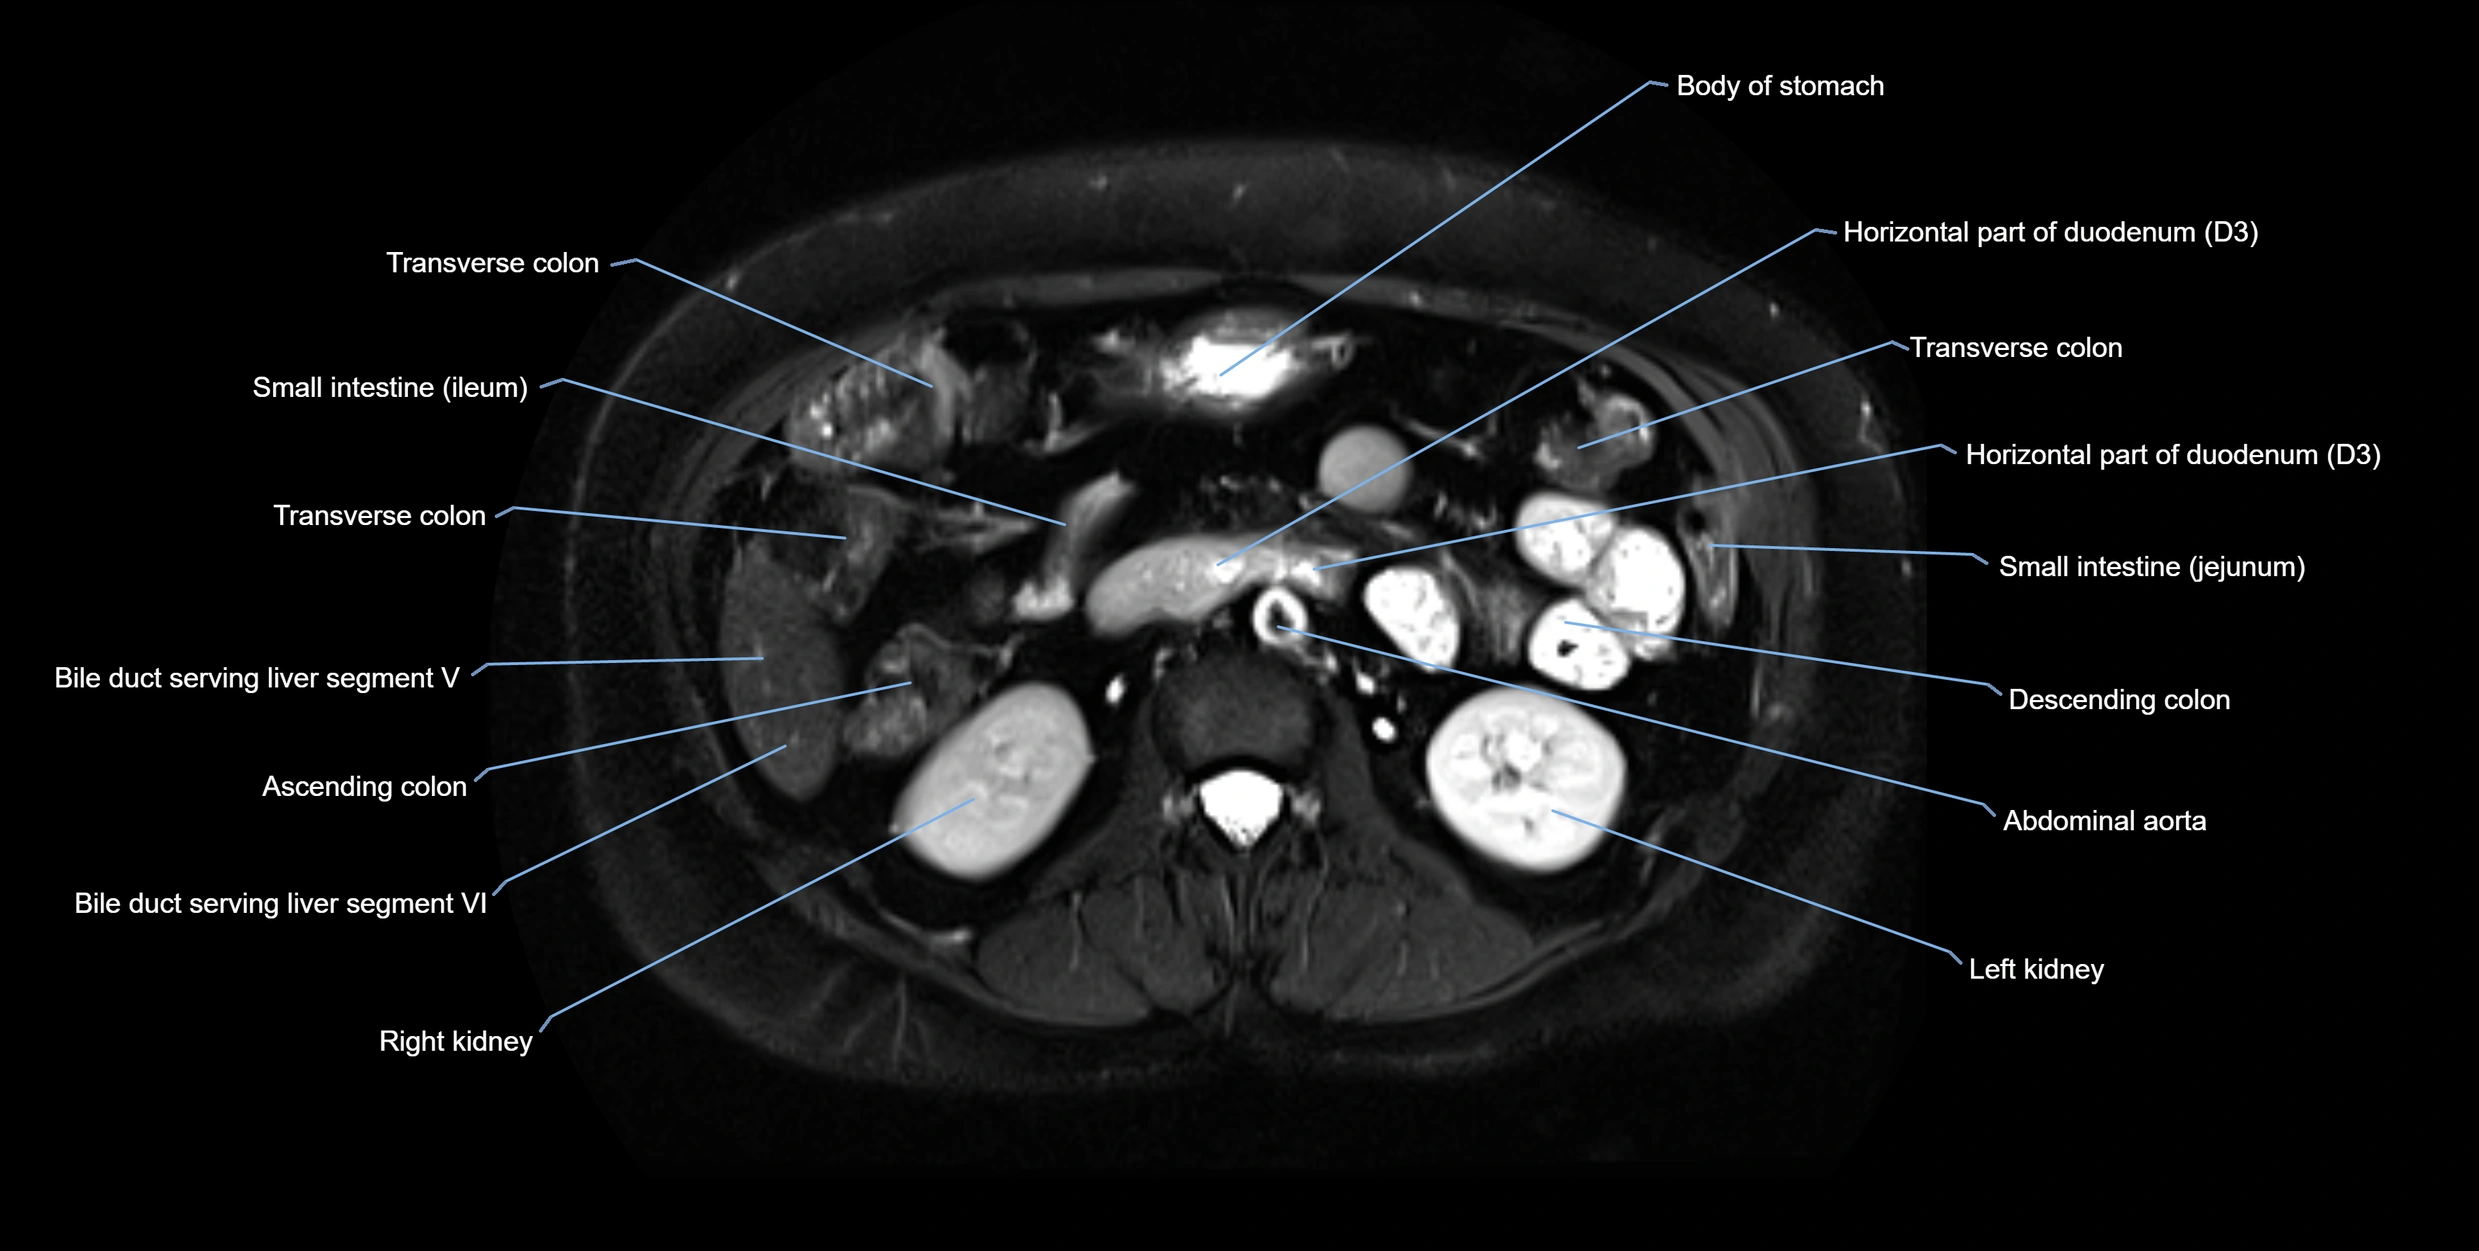

MRI image

image